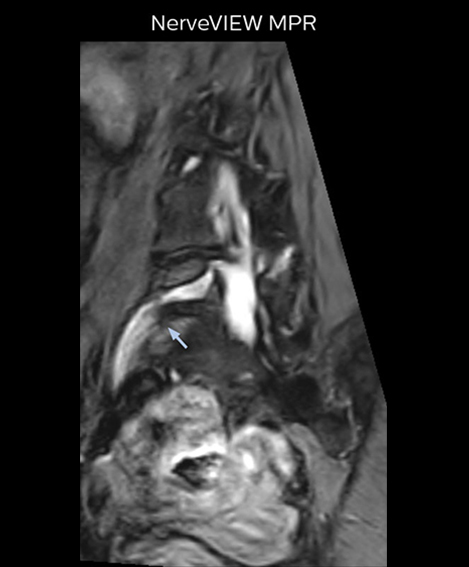

“The intra-luminal signal of veins, especially around the intervertebral space, can be suppressed well with NerveVIEW. As a result, we can easily observe the detailed nerve structure around the posterior ganglion,” he says. “This is why we use 3D NerveVIEW for intraforaminal stenosis and extraforaminal stenosis/herniation (lateral disc herniation). On the other hand, if herniation is suspected to exist inside the dorsal root ganglion (DRG), balanced TFE or ProSet-FFE is applied. NerveVIEW is not suitable for evaluating the median type of herniation.” The SE-EPI DWI-based method for MR neurography works well for large FOV exams like whole-body MRI, but focal examination of nerves is often limited by the attainable spatial resolution (both inplane and slice direction) and geometric distortion. “3D NerveVIEW achieves higher in-plane resolution – close to our other routine spine sequences – and the source images can be used instead of adding a fat-suppressed T2-weighted sequence,” Tanji says.

“Recently, the two surgical methods extreme and oblique lateral interbody fusion (XLIF and OLIF) have become mainstream for minimally invasive treatment of lumbar spinal canal stenosis and intervertebral foramen stenosis. With these surgical techniques, the spine is approached from the flank, and prior knowledge of the exact anatomy of the lumbosacral plexus would be extremely helpful. To that end, high slice resolution (less than 1 mm acquisition) that enables sharper sagittal MPR images will be needed.”

“For both brachial and lumbar plexus, we are currently using a 230 mm FOV and voxels of about 1 x 1 x 2 mm acquired (1 x 1 x 1 mm reconstructed). This provides us a good representation of the nerves, even though this FOV is relatively small. Regarding the inplane resolution, we hope to be able to bring that down to 0.7 mm, similar to our typical 2D multislice T2W images,” says Tanji.

Implementing NerveVIEW without lengthening exam time “The source images of NerveVIEW exhibit a contrast similar to STIR or fat-suppressed T2-weighted images. So, in our neurography exams we are replacing the 2D T2-weighted coronal sequence with 3D NerveVIEW. With this, we add a lot of useful information without adding scan time. This is important for patients with severe lower extremity symptoms, as they often find it difficult to maintain still during the whole MRI examination, so the exam should be as short as possible.” “We have currently implemented 3D NerveVIEW on our Achieva 3.0T dStream MRI system only. Because the 3D NerveVIEW method is based on a background signal suppression technique, we decided to use the high SNR of our 3.0T MRI system for obtaining the best possible visualization of peripheral nerves,” says Tanji. “Where NerveVIEW of the lumbar plexus is currently used as a subroutine scan for patients with strong lower limb symptoms, its use for visualization of the brachial plexus, is currently limited to special cases such as schwannomas and neuritis, usually only 1 or 2 cases per month.”